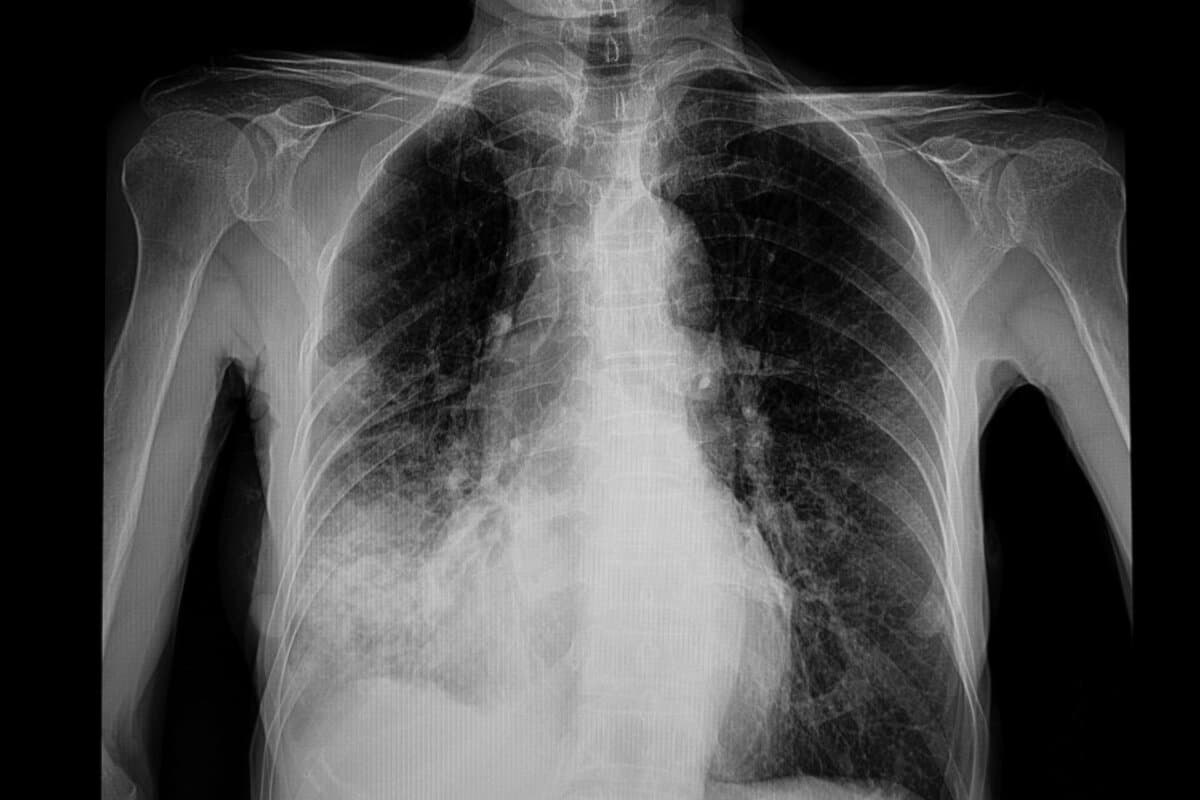

La pneumonie communautaire (CAP, Community-Acquired Pneumonia) est une cause fréquente d’hospitalisation. Elle peut être déclenchée par différents agents pathogènes tels que des bactéries, des virus ou des champignons. Le traitement est d’autant plus délicat que la cause exacte reste souvent indéterminée. Le processus pathologique s’explique par la lésion tissulaire directe causée par les agents pathogènes et par la surréaction immunitaire de l’organisme. C’est surtout cette dernière qui est à l’origine de la mortalité élevée associée à cette maladie.